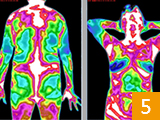

治疗前后炎症对比图/ Inflammation contrast

• 治疗前

• 治疗后